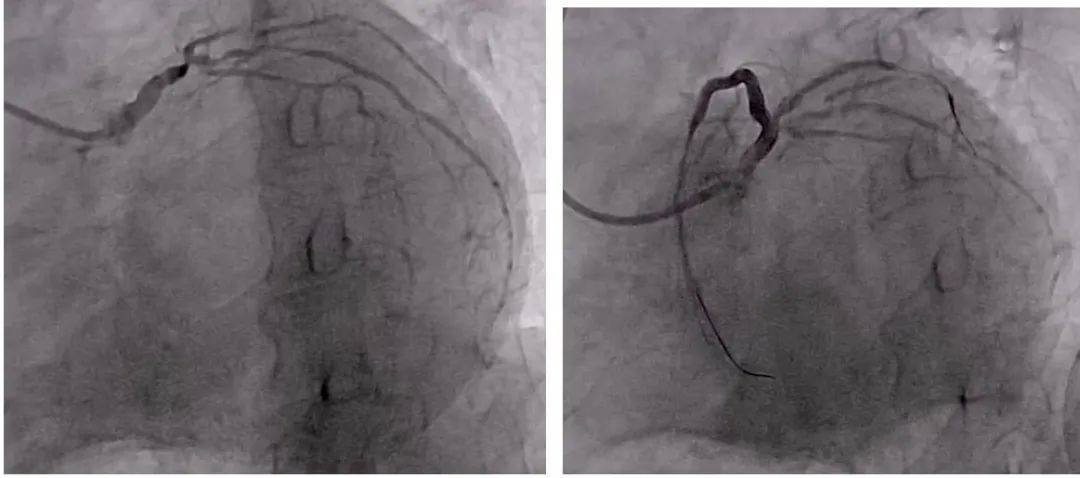

然而 , 当冠状动脉造影完成后 , 医务人员一度陷入沉默 。 因为3年来一直没有进行干预与治疗 , 现在陈叔的病情十分严重:心脏冠状动脉的左主干末端重度狭窄 , 前降支开口慢性完全闭塞 , 中间支、回旋支存在重度狭窄和严重钙化 。 这样的情况 , 正是陈叔命悬一线的原因 。

心脏重症科负责人靳文、主治医师陈武奇沉着冷静 , 使用多种生命支持药物 , 及时给予溶栓、止痛 , 经过反复多次尝试 , 最终顺利开通了慢性闭塞的严重狭窄病变血管 。 术前病变严重的冠状动脉病变 , 恢复了清晰的正常结构、顺畅的血流和充分的血流量 。

术前术后冠脉造影对比